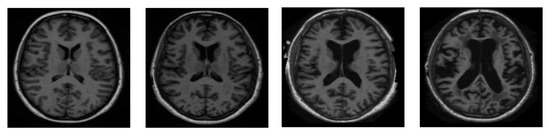

The very first stage of the suggested methodology is the acquisition of an image, in which an MRI image is used as an input for processing. In the application of the suggested methodology, brain tumor MRI images have been used. Four datasets containing T1-w and T2-w contrast-enhanced MRI images of three kinds of brain tumors were used. Images in the MRI format are stored in MATLAB R2021a, 255 × 255 in size, and they are shown as RGB images of grayscale as the ranges of their entries are from 0 to 1. Here, the black image is represented by 0 while the white image is represented by 1. Entries between 0 to 1 represent the variation in intensity from black to white (see Figure 2).

Figure 2.

Original normal brain T1-weighted and T2-weighted MRI images.